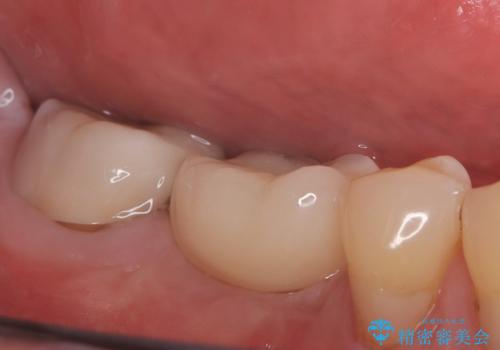

- 奥歯の欠損をインプラントで治療したいと来院された患者様です。

骨の状態が安定するまで待機したのち、インプラントを埋入しています。

スクリューリテインにて上部構造を連結しています。